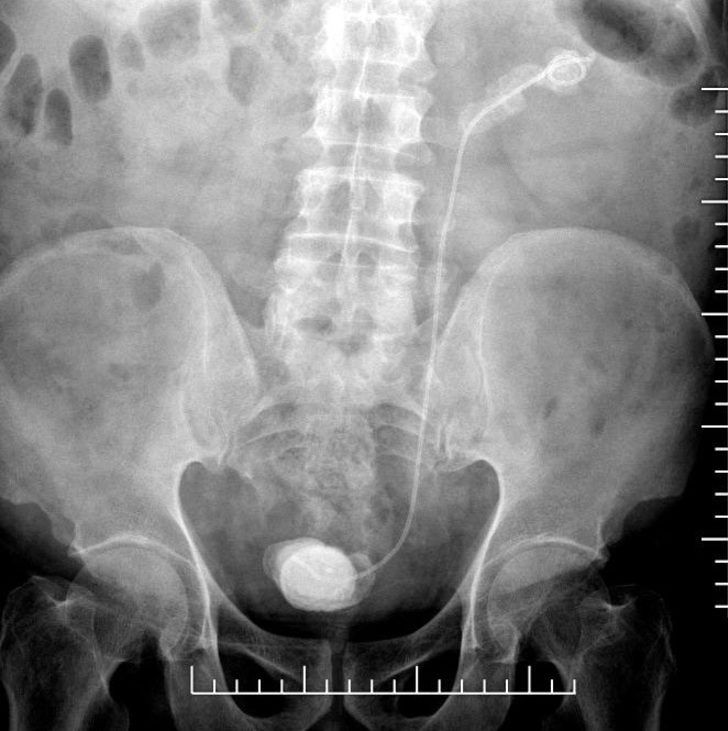

Elazığ’da yaşayan 3 çocuk babası Kadir Elban (69), idrar tutamama ve yanma şikayeti ile Fethi Sekin Şehir Hastanesine başvurdu. Burada Üroloji Uzmanı Op. Dr. Kadir Yıldırım tarafından tetkikler sonucu Elban’ın böbrek kanalında 28 santimetre stent olduğu, stendin etrafında ve mesanede taş oluştuğu fark edildi.

Dr. Yıldırım'ın hastaya sorması üzerine Elban’ın 7 sene önce Ankara’da bir hastanede bağırsaklarından ameliyat olduğu ve stent takıldığı öğrenildi. Bunun üzerine Op. Dr. Yıldırım tarafından yapılan operasyonla unutulan stent ve etrafındaki taşlar alındı.

Hastanın 7 yıl önce bağırsak operasyonu geçirdiğini belirten Op. Dr. Kadir Yıldırım, “Bu işlem sırasında DJS stent uygulanıyor ve 1 ay içerisinde alınması gerekiyor. Bu stent bazen hekim veya hasta kaynaklı unutulabiliyor. Bu hastamızda da böyle bir talihsizlik olmuş.

7 yıl boyunca böbrekte ve kanalında kalmış. Bu süre zarfında böbreklerde ileri boyutta taşlaşma olabiliyor. Bu tür durumlarla dünyada ve ülkemizde karşılaşılabiliyor. Bu hastanın tedavisinde endoskopik ameliyatlar dizisi ile tek seansta taşsızlık sağladık ve stendi çıkardık.

İlk başta böbrek kanalındaki taşlar lazer ve pnömotik litotriptör (havalı sistem ile taş kırma işlemi) ile kırıldı. Takiben böbrek üst polündeki 7 santimlik taş, fleksibl renoskop ile kırıldı” dedi.

Mesanede de 8 santimlik bir taşın oluştuğuna değinen Op. Dr. Yıldırım, “Bunu küçük bir kesi ile çıkardık. Hastamızın genel durumu iyi ve takiplerimize devam ediyoruz. 7 yıl çok ciddi bir süre. Aslında 1 yıl bile geç denilecek bir zaman ama 7 yıl kalmış. Hasta hem şanssız hem de şanslı. Böbreği tamamen kaybetmiş olabilirdik. Bazen bu durum ciddi enfeksiyon ataklarına yol açabilir. Böbreğin alınmasına kadar gider durumlara yol açabiliyor.

Böbrek fonksiyonlarına bir miktar etkilenme olsa da stendi çıkardığımız takdirde devam edebilecek düzeyde sağlıklı böbrek parenkimi vardı. Bu şekilde stendin çıkartılması hastanın tedavisi için yeterli” diye bilgi verdi.